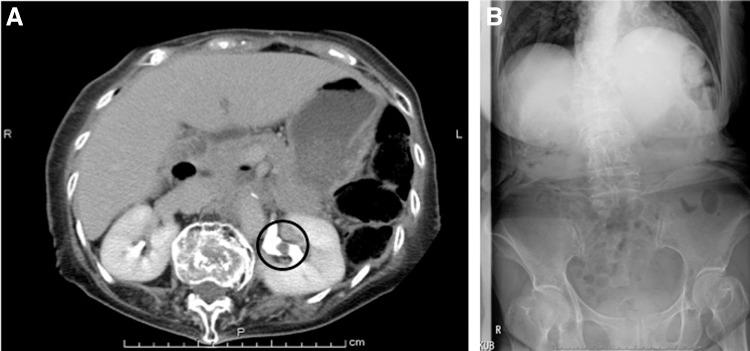

Kyphosis is usually described as the deformity of the spine that results in an abnormally round back. Patients with kyphosis form a challenging group to laparoscopic surgeons because of difficulties in positioning and abdominal approach. The narrow abdomen causes difficulty with trocar insertion and some operative procedures. Here we report the transperitoneal complete laparoscopic nephroureterectomy in a case of kyphosis. An 81-year-old woman underwent this operation for urothelial carcinoma of the upper urinary tract. We took best care of the positioning and the trocar insertion; we could have accomplished utilizing four ports at semilateral position without any troubles and complications. This procedure is safe and feasible, and not thought to be a contraindication for the patients with senile kyphosis.